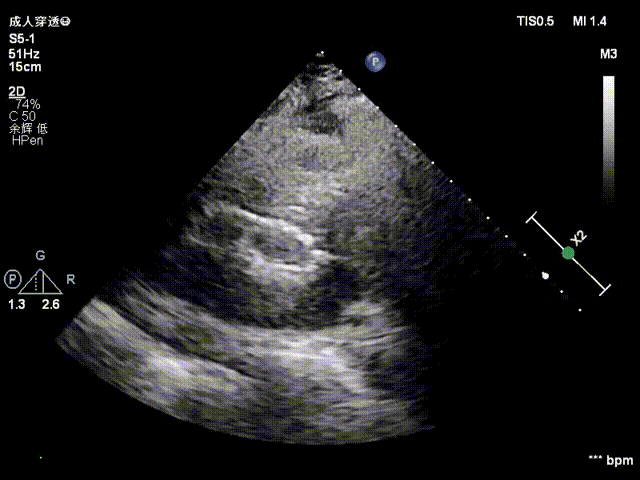

超声评估

植入后超声评估:植入位置良好,无明显瓣周漏

超声多切面评估,血流动力学改善明显,无瓣周漏